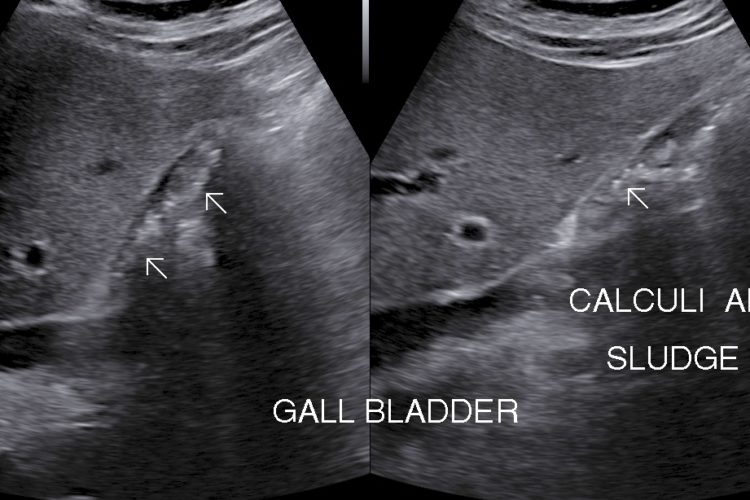

• Cholecystitis: Cholecystitis is Inflammation of gall bladder. Acute calculus cholecystitis results when calculus/calculi get impacted at neck of gall bladder or cystic duct.

• Symptoms: Right upper abdomen, nausea, vomiting & fever(sometimes)

• Finding: Sonography shows thickened oedmatous walls of gall bladder & impacted calculi. Sludge, pericholicystic fluid , localized abscess are additional findings. Sometimes gall bladder is so overdistended that impacted calculi may not be visualized.